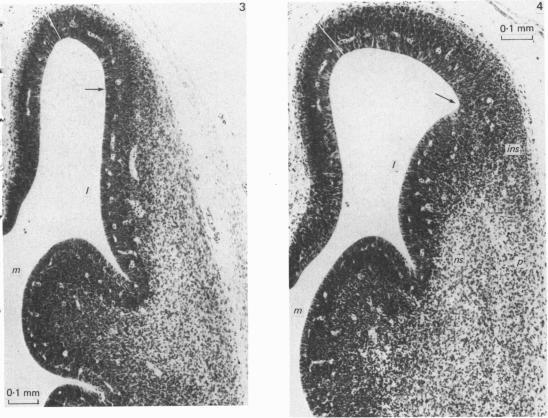

小鼠端脑侧壁的生长模式。II. 等皮质神经元产生期间及之后的组织学变化。

Growth patterns in the lateral wall of the mouse telencephalon. II. Histological changes during and subsequent to the period of isocortical neuron production.

The histogenesis of the isocortical segment of the lateral telencephalic wall at the coronal level of the interventricular foramen was studied in mice between the ages of E10 and the adult. The proliferative activity of the periventricular germinal layers was correlated with changes in cell distributions in the intermediate layer. The appearances were consistent with a wave of differentiation moving across the ventricular layer from lateral to medial and a peak of neuron production occurring about E13. The sequence of changes was analysed using the concept of a radial unit composed of ventricular cells and their related progeny of neurons. The observed histological changes were interpreted as the result of radial units of similar productive history entering and completing the histogenetic sequence at successively later times along a lateromedial gradient. Some of the implications of this approach were examined and discussed in relation to the general evolutionary properties of such a system of histogenesis.

在E10期至成年期的小鼠中,研究了室间孔冠状水平外侧端脑壁等皮质段的组织发生。室周生发层的增殖活性与中间层细胞分布的变化相关。这些表现与分化波从外侧向内侧穿过室层以及约E13期出现神经元产生高峰一致。利用由室细胞及其相关神经元后代组成的径向单元概念分析了变化序列。观察到的组织学变化被解释为具有相似产生历史的径向单元沿着外侧-内侧梯度在相继较晚的时间进入并完成组织发生序列的结果。探讨并讨论了这种方法的一些含义与这种组织发生系统的一般进化特性的关系。